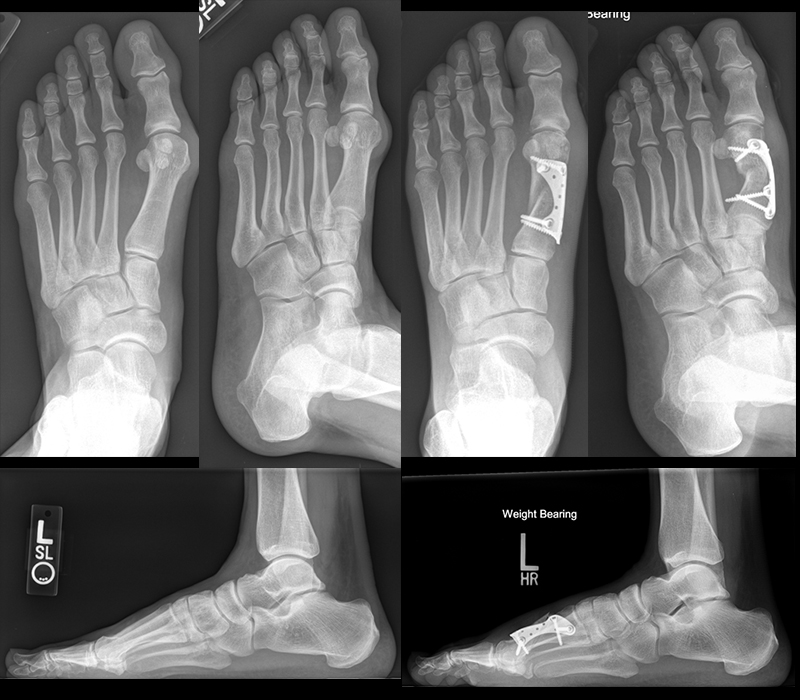

Die eigenständige Bewegung und Mobilisation im Großzehengrundgelenk und Interphalangealgelenk kann durch Physiotherapie, Lymphdrainage und Gangschule unterstütz werden. Eine radiologische Kontrolle erfolgt zur Dokumentation des Operationsergebnisses intraoperativ und nach 6 Wochen im Konfektionsschuh.

Zum Lesen der Bildbeschreibung und zur Vollansicht bitte das Bild anklicken. Bild: Markus Walther.